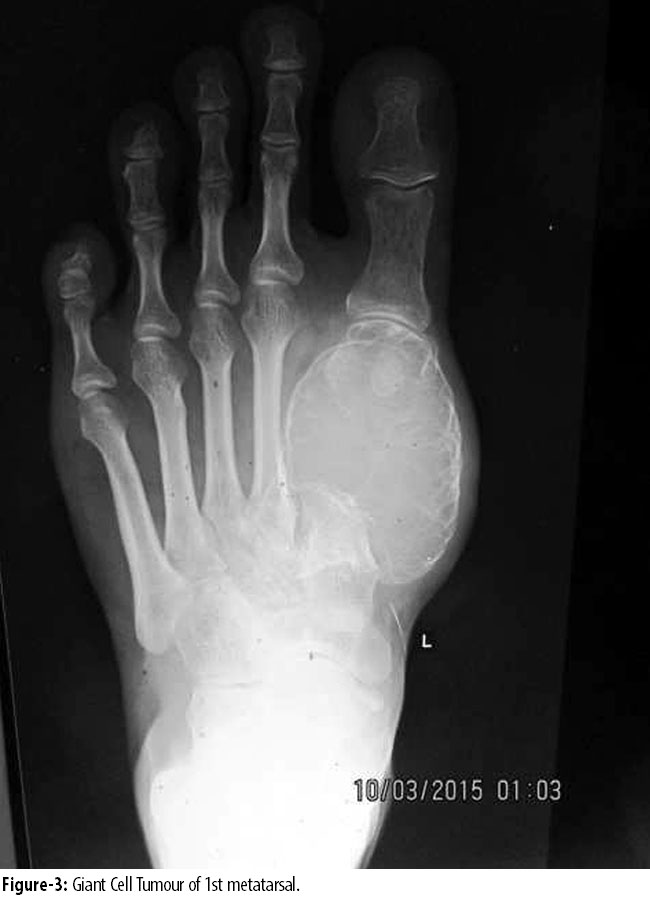

Duration of symptoms ranged from 4 to 12 months with a mean of 6.54 months (SD 4.08). All the tumours presented as expansile lesion, destroying cortex in 8(3.3%) cases. In all cases, lesion was more than half the diameter of the bone and thickness of sub-chondral bone in adjacent articular surface was less than 5mm to 0mm. All of them had extension into the soft tissue. Open biopsy was performed in 7(2.9%) cases. In 6(2.5%) cases, fine needle aspiration cytology (FNAC) was diagnostic, showing giant cell lesion. 1(0.4) calcaneal giant cell tumour was treated by extended curettage and filling the cavity with fibular head compact bone graft. Other 2(0.8%) cases of calcaneal giant cell tumour were treated by complete resection of calcaneus. 1(0.4%) case of talus GCT was treated by curettage and bone grafting. Out of 7(2.9%) cases of metatarsals, 4(1.6%) were in 1st metatarsals, 2(0.8%) in 2nd metatarsal and 1(0.4%) in 3rd metatarsal. 2(0.8%) GCTs in 1st metatarsal (Figure-3 and 4)

and 1(0.4%) in 2nd metatarsal were in stage3 (Figure 5 and 6),